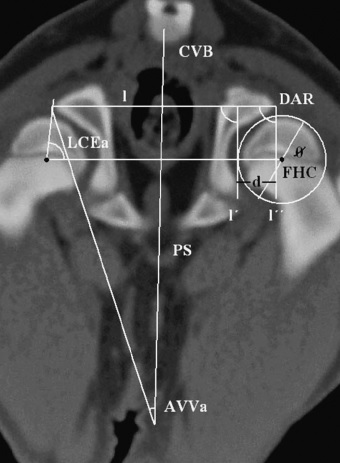

Dysplazje stawów biodrowych

Dysplazje stawów biodrowych polegają na nieprawidłowym dopasowaniu głowy kości udowej do panewki stawu biodrowego. Prowadzi to do niestabilności stawu oraz stopniowego uszkadzania chrząstki stawowej, a co za tym idzie, powstawania zwyrodnień i powstawania biodra płaskiego (coxa plana).

Diagnostyka dysplazji

Rozpoznanie dysplazji opiera się na badaniu ortopedycznym oraz diagnostyce obrazowej. Najczęściej stosowane badania to:

- badanie kliniczne i ortopedyczne,

- badanie rentgenowskie (RTG),

- tomografia komputerowa (TK),

- artroskopia diagnostyczna.

Badania te pozwalają ocenić stopień zmian oraz zaplanować odpowiednie leczenie.